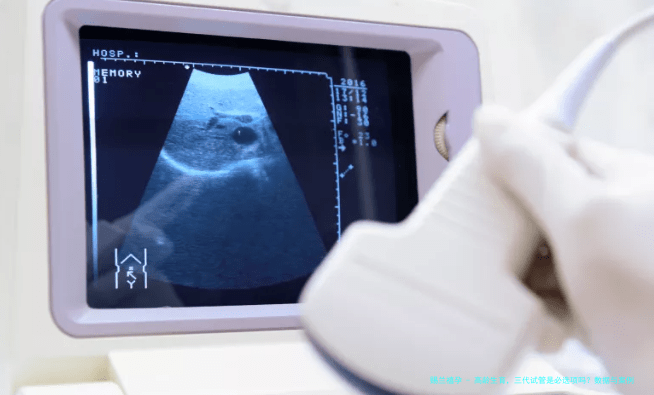

三代试管,简单来说,就是在胚胎植入子宫前,先做个“体检”,筛查一下有没有遗传疾病或染色体问题。这技术听起来高大上,其实原理不复杂:通过提取胚胎细胞进行基因分析,只选择健康的胚胎移植。它的优势很明显,能降低宝宝出生缺陷的风险,尤其对高龄女性来说,可能是个不错的选择。例如,有研究显示,使用三代试管后,40岁以上女性的活产率可以从自然状态的10%提升到20-30%。但要注意,这不是万能的,它不能保证100%成功,而且费用较高,过程也可能带来心理压力。